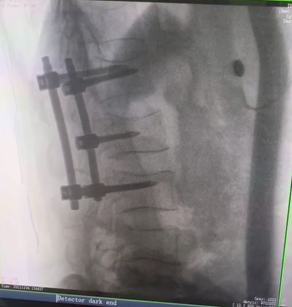

例如治療先天性脊柱側(cè)后凸畸形,由于脊柱自身復(fù)雜的解剖結(jié)構(gòu)限制,使得脊柱外科手術(shù)對(duì)于精確度有著較高要求。以往我們只能采用傳統(tǒng)的正側(cè)位圖像來判斷螺釘置入的位置,現(xiàn)在三維C形臂特有的類CT斷層成像,使得治療過程可視化,立體化,在術(shù)中非常直觀地判斷螺釘植入的準(zhǔn)確度??捎行б龑?dǎo)術(shù)者植入后路螺釘并切除半錐體。同時(shí)可以在術(shù)中實(shí)時(shí)驗(yàn)證手術(shù)效果。有效地縮短了手術(shù)時(shí)間,降低手術(shù)風(fēng)險(xiǎn),避免了不必要的術(shù)后翻修手術(shù)。

另外,三維C形臂采用12英寸(30cm x 30cm)的平板探測器,成像區(qū)域大,有效成像面積比9英寸傳統(tǒng)影增提升了100%,可一次拍七節(jié)頸椎、五節(jié)腰椎、十二節(jié)胸椎、雙側(cè)骶髂關(guān)節(jié)、股骨頭及單側(cè)盆骨。